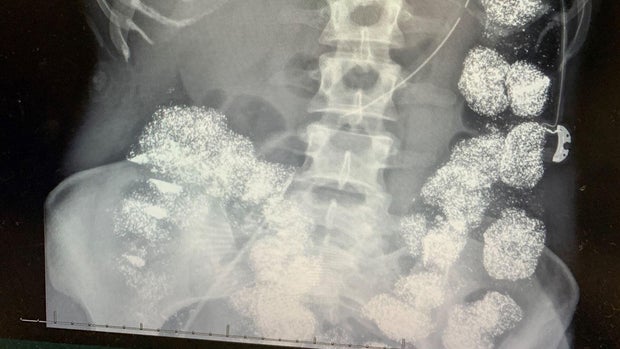

Doctors showed him Hannah's X-rays.

Anne Marie Green: What did you think?

Lt. Alan McDearmond: Oh, gosh, I was just floored. I mean, her whole insides was lit up from the — the lead reacting to the X-ray … I mean It was crazy.

Nicole Pettey: They said her colon was so packed, full of lead … it was almost 100% lead. … there was no room in her stomach to hold anything. It was just complete lead plus there was lead just in her bones, just everywhere …